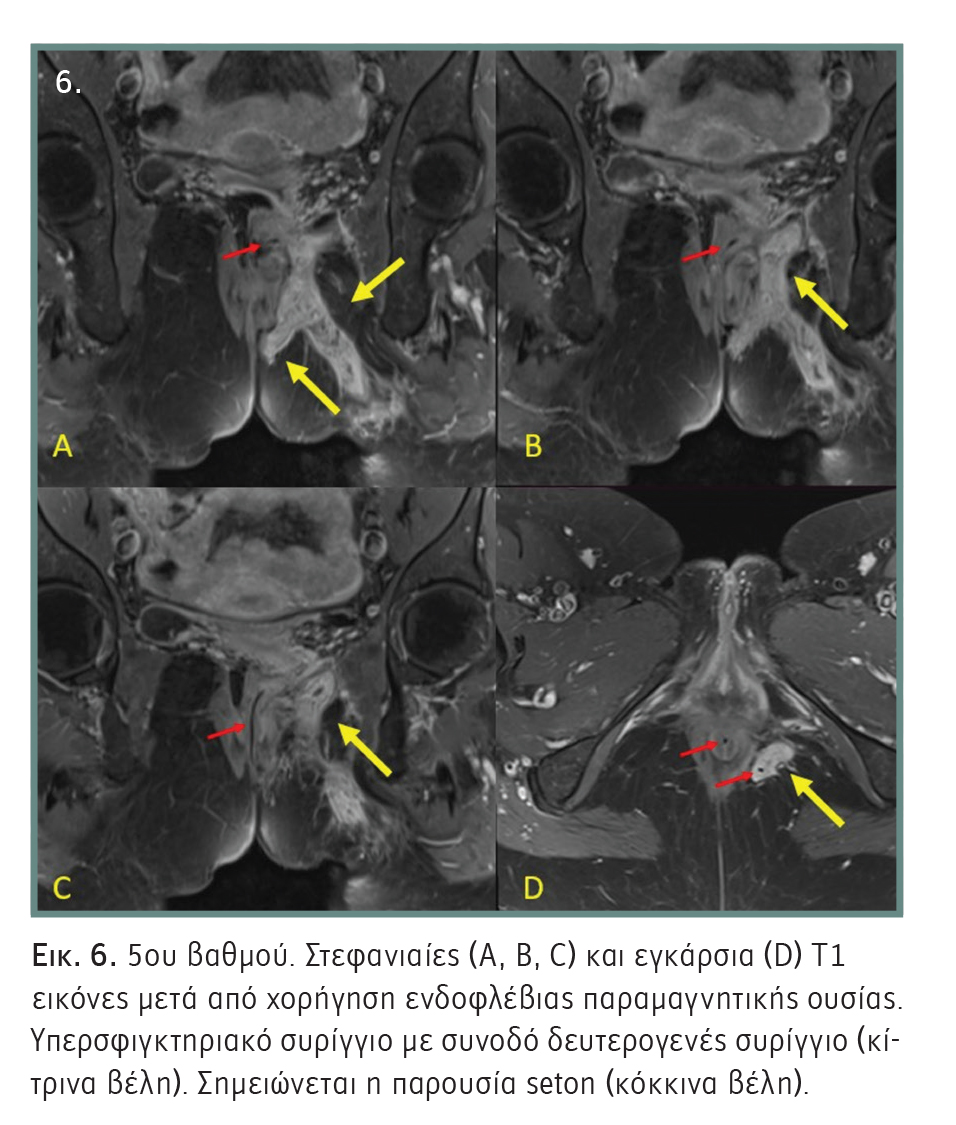

- 1ου βαθμού: Απλό γραμμικό μεσοσφιγκτηριακό συρίγγιο, το οποίο εκτείνεται από τον πρωκτικό σωλήνα μέσω του μεσοσφιγκτηριακού χώρου έως το δέρμα του περινέου. Δεν υπάρχει διακλάδωση του πόρου εντός του σφιγκτηριακού συμπλέγματος. Ο συριγγώδης πόρος περιορίζεται πάντοτε στον μεσοσφιγκτηριακό χώρο (Εικόνα 2).